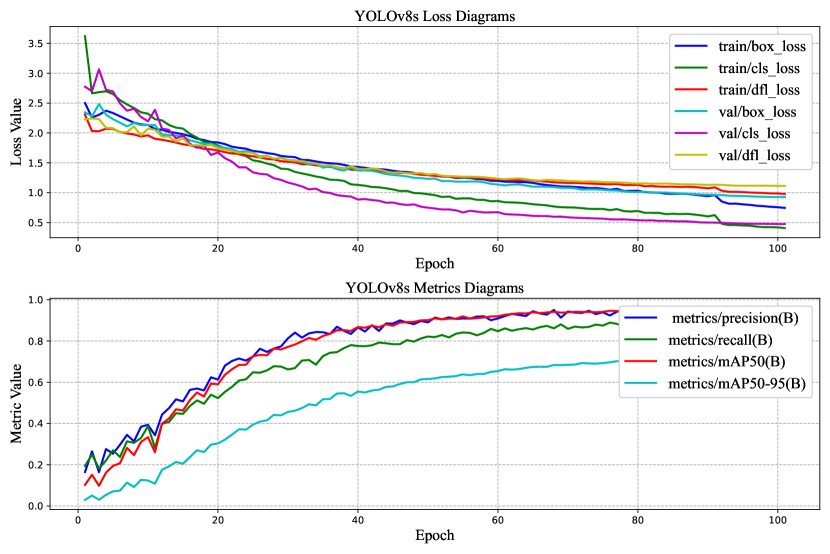

For the cervical vertebrae fracture detection, the models are trained 100 epochs and the results are demonstrated in Table 3.

mAP50 is the Mean Average Precision (mAP) at an IoU threshold of 0.5. IoU (Intersection over Union) is a metric used to measure the overlap between a predicted bounding box and a ground truth bounding box. A higher IoU threshold means that the predicted bounding box must overlap more with the ground truth bounding box to be considered a true detection. mAP50-95 is the Mean Average Precision (mAP) at IoU thresholds from 0.5 to 0.95. This is a more comprehensive metric than mAP50, as it takes into account the model’s performance at a wider range of IoU thresholds. Equations 4, 5, 6, and 7 define the formulas for mAP50, mAP50-95, Recall, and Precision.

For fracture detection based on the results, it is clear that the performance of YOLOv8 outperforms YOLOv5. This is a significant improvement, especially considering that YOLOv8 is also faster than YOLOv5. Furthermore, although YOLOv8m has more parameters the mAP50 for YOLOV8s is a bit higher. On the other hand, YOLOv8m has higher mAP50-95. It is evident that YOLOv8s has demonstrated a strong ability to correctly classify images as “Normal" with 194 true positives and only 6 false negatives as presented in Figure 9.

However, it tends to make more errors when classifying images as “Fracture," as indicated by 97 false positives and 1347 true positives. This can be attributed to the nature of medical image analysis, where the cost of missing a “Fracture" (false negatives) may be considerably higher than misclassifying a “Normal" image as a “Fracture" (false positives). YOLOv8m, on the other hand, demonstrates a similar trend but with slightly improved performance when compared to YOLOv8s. It correctly classifies 192 “Normal" images and 1353 “Fracture" images. However, it still makes some errors, with 8 false negatives for “Normal" and 91 false positives for “Fracture". This model appears to strike a better balance between precision and recall for both classes, indicating a more robust classification performance.